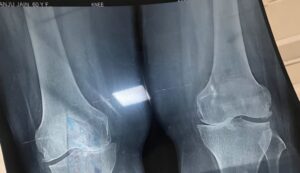

विशेषज्ञ चिकित्सकों की टीम – डॉ. ऋतूज अग्रवाल, डॉ. अभिलाष यादव, डॉ. टिंकु सिंह तथा सीनियर रेजिडेंट डॉ. दिव्यम अग्रवाल, एनेस्थीसिया विशेषज्ञ डॉ. शाहरूख और डॉ. नीलम एवं ओटी टेक्नीशियन योगेन्द्र – के समर्पित प्रयासों से यह सुविधा सुचारू रूप से संचालित हो रही है। हाल ही में 65 वर्षीय श्रीमती अंजू जैन, निवासी उझानी, जनपद बदायूँ, को मेडिकल कॉलेज लाया गया। वे विगत दो वर्षों से बाएं घुटने में असहनीय दर्द एवं चलने-फिरने में कठिनाई की समस्या से जूझ रही थीं। डॉ. टिंकु सिंह द्वारा उन्हें घुटना प्रत्यारोपण की सलाह दी गई। दिनांक 18 जुलाई 2025 को उन्हें आपात स्थिति में भर्ती किया गया और अगले ही दिन सफल ऑपरेशन किया गया।